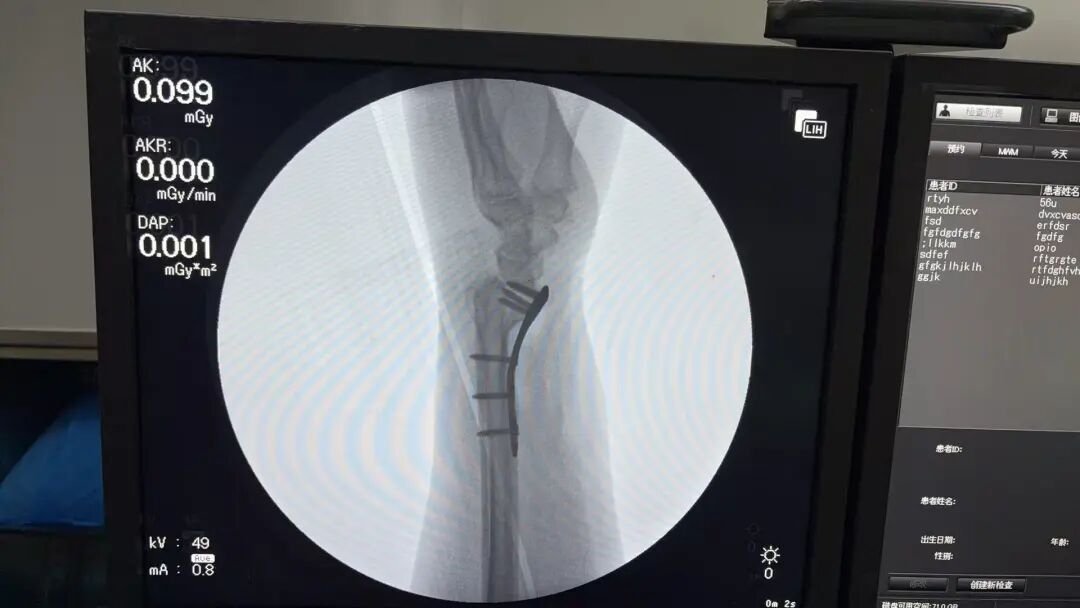

作为医院救治的“前哨”,急诊科依然是一片紧张而有序的忙碌景象。急救绿色通道24小时畅通无阻,医护人员严阵以待,大年初二急诊救治一位脑出血患者,为生命救援赢得了宝贵时间。